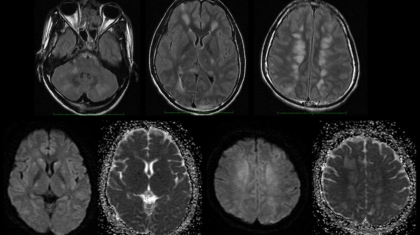

20 year old male patient presented with headache for 2 days, altered sensorium and single episode of seizure. He had a major road traffic accident one week back.